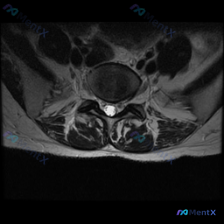

看到一张很典型的腰椎MRI轴位片,关于椎间盘病变的观察,整理了完整读片思路和分析,分享给大家。 病例影像基础信息 这是一张腰椎MRI的T2加权轴位图像,层面为腰椎间盘水平。 影像观察核心发现 1. 椎间盘结构:中心前方的椎间盘T2信号较正常髓核降低,呈灰黑色,提示椎间盘脱水退行性改变 2. 突出情况...

看到这张腰椎MRI-T2轴位影像,大家第一反应是什么?问题问的是椎间盘病变,整理一下分析思路和大家分享。 一、影像基本信息 这是腰椎椎间盘层面(最可能为L4/5或L5/S1)的T2轴位扫描,我们先梳理所有客观发现: 1. 椎间盘情况:中央区域信号较正常稍低,提示椎间盘脱水变性;但后缘形态完整,没有明...

刚整理完这份腰椎MRI轴位片的分析,整个思路挺典型的,分享给大家一起讨论。 病例基本影像信息 这是一份腰椎MRI的T2加权轴位(横断面)扫描,层面位于腰椎间盘层面,可观察到的结构包括:前方椎体后缘、中部椎管内含硬膜囊、双侧关节突关节、后方椎板棘突以及两侧背肌。 核心影像发现 1. 椎间盘改变:椎间盘...